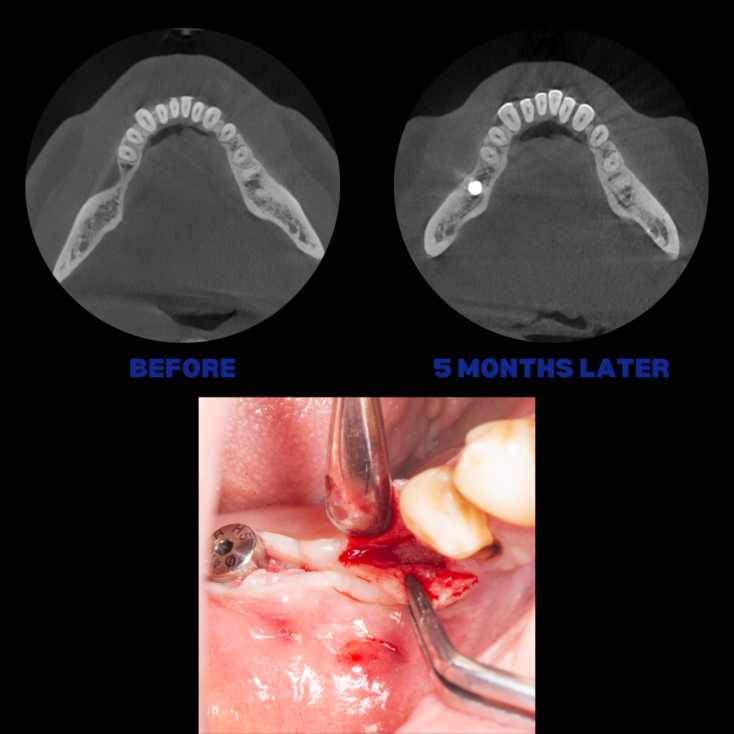

İmplant etrafındaki kemik açıklığını kemik grefti ile tedavi ettiğimiz vakamız